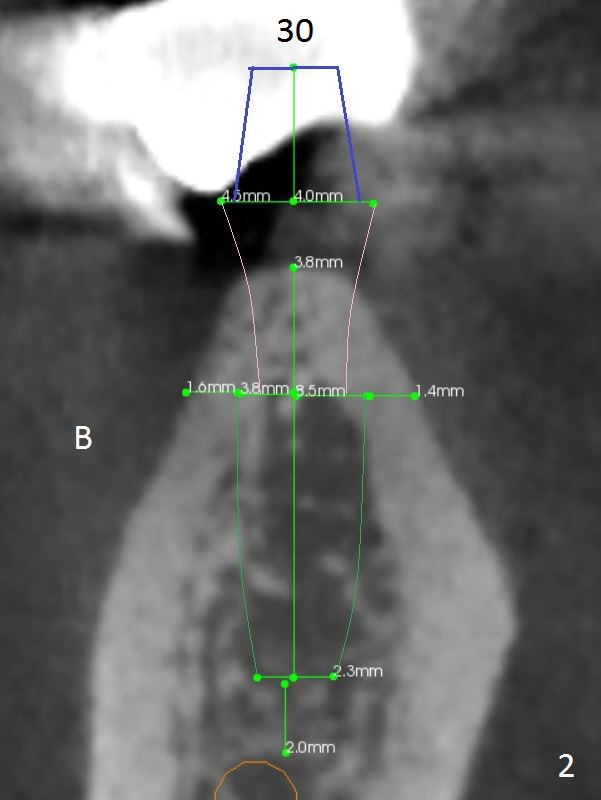

The ridge at #30 is pointed (Fig.2) and going to be resected (Fig.3 black area) to receive a narrow, short implant (3.8x8.5 mm).   A splinted immediate provisional will be fabricated following placement of a 4.5x4(5) mm abutment at #30 (Fig.2,3).  Take Alginate impression when the patient arrives in case the tooth #31 is also non-salvageable.